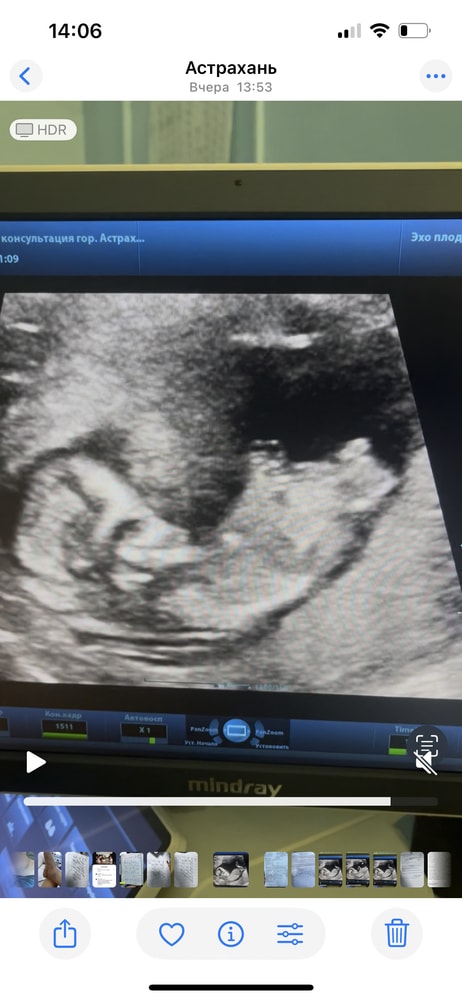

Я бы сказала девочка - половой бугорок вроде параллелен позвоночнику.

Тут вообще не сразу сообразишь, что есть что)) Но если то что я вижу - половой бугорок - девочка, скорее всего.

мне пол показывали не на таком виде. А как бы вид попы снизу. Соответственно если между ножек есть что-то, то мальчик, а если нет, то девочка. Думаю, на таком снимке ничего не разглядеть, или ошибочно можно увидеть

ну вот если на УЗИ это половой бугорок виден,то похоже девочка